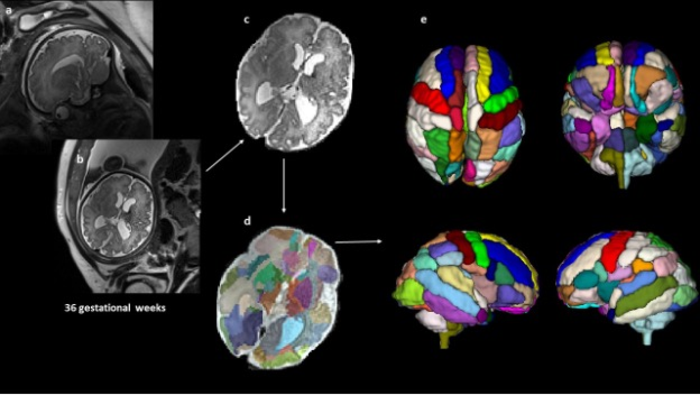

To find out if brain scans taken prenatally could help identify signs of ASD earlier, the researchers retrospectively analyzed 39 fetal MRI brain scans taken at Boston Children’s Hospital. Nine of the children were later diagnosed with ASD, 20 were neurotypical and 10 did not have ASD but had other health conditions that were also observed in the children with ASD. The brain scans had been taken at about 25 weeks’ gestation, on average.

After preprocessing, the researchers used an atlas-based automated anatomical labeling method to segment the brain scans and then compared the segmented brain regions between the different groups. The biggest differences were found in the brain’s insular lobe, which had a significantly larger volume in the ASD group compared with the other three control groups. The insula is a region deep inside the brain that is thought to have a role in perceptual awareness, social behavior and decision-making, among other functions.

The findings align with other recent studies that have reported changes in the insular cortex in adults with autism and suggests these differences may begin in the womb. The researchers also found that the scans from children with ASD showed a significantly larger amygdala and hippocampal commissure compared with children who had other health conditions but not ASD.